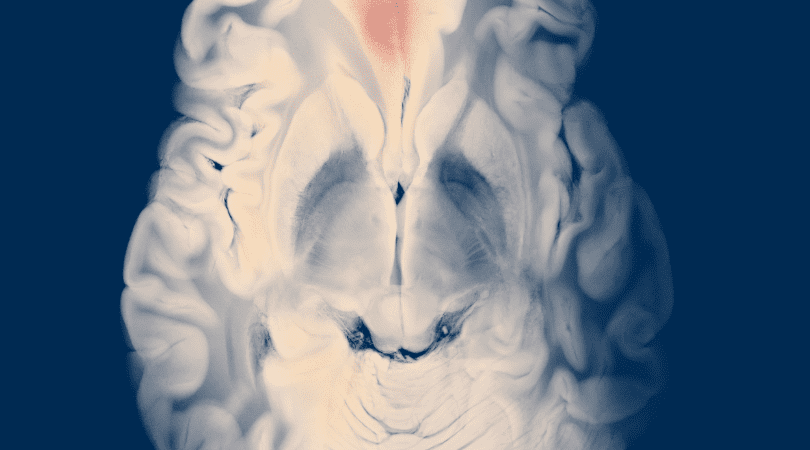

تفصيل: اختيار العلاج يعتمد على الفحوصات (صورةٍ بالموجات فوق الصوتية واختبارات هرمونية).